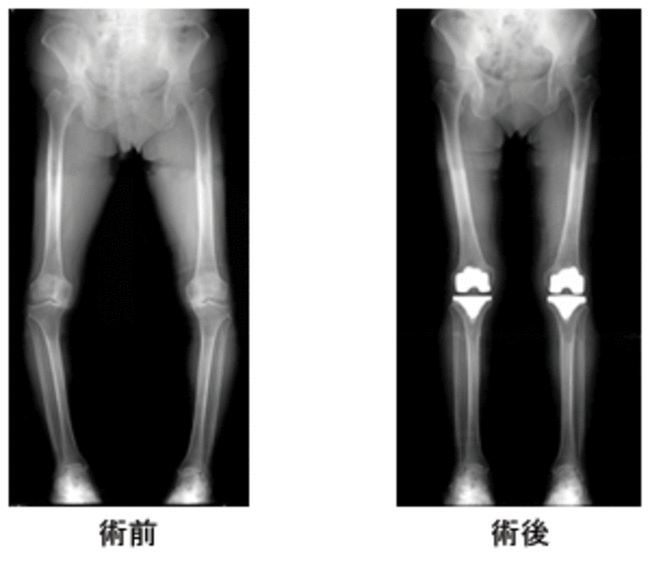

手術症例の手術前・手術後のレントゲン写真

変形性膝関節症の進行度を示しますが、第3段階、あるいは第4段階においては、人工関節置換術による治療が勧められる状態と言えます。人工膝関節置換術とは、痛んだ膝関節部の骨・軟骨の代わりに、丈夫な金属、ポリエチレン製のインプラントを挿入し、新たな膝関節を形成する手術です。この手術を行うための器具は特殊なものですが年々改良、洗練され、またインプラント自体の品質も向上し、安全にかつ確実に痛みをとることのできる手術の1つである証拠として、手術件数が年々増加しており、近年では全国で年間10万件以上の手術が行われています。

治療はグレードⅢまでは投薬、関節内ヒアルロン酸注入などの保存的治療が、ⅡからⅢは軟骨がまだ残っているので体重を健常な外側にシフトさせる外反骨きり術、Ⅳ、Ⅴは軟骨が欠損しているので人工関節置換術の適応となります。変形が内側に限局している場合には片側置換術も選択されます。